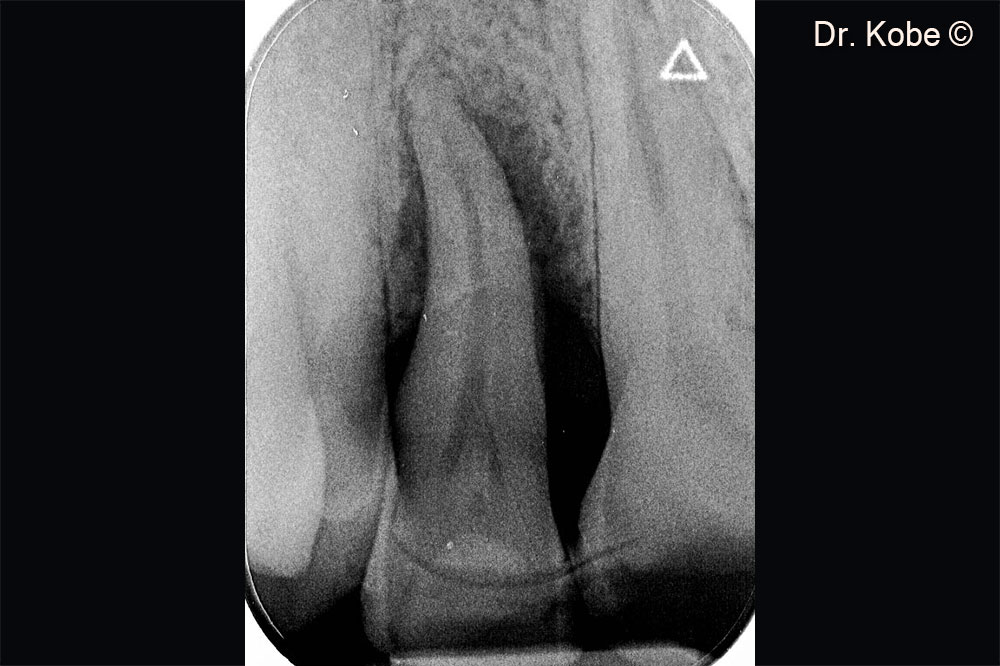

Vertical bone defect on the radiograph